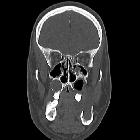

developmental and genetic origin affecting the paediatric craniofacial skeleton. Typical manifestations of nevoid basal cell carcinoma syndrome (NBCCS) in a 16-year-old boy. a Orthopantomography (OPT) shows cystic lesions of the mandible and maxilla (arrows), with unilocular and multilocular pattern and smooth or scalloped borders associated with displaced and unerupted permanent teeth. b Coronal CT scan (bone window) shows ectopic calcifications of the falx cerebri and tentorium cerebelli (arrows) and spotted meningeal calcifications (arrowheads). Brain MRI reveals a cavum veli interpositi on axial T2 (asterisk in c) and coronal contrast-enhanced T1 (asterisk in d) and also vermian dysgenesis (arrowheads in d)